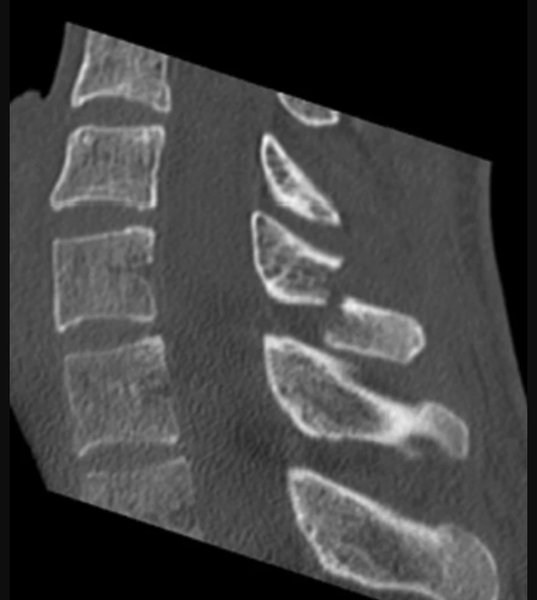

31-летний мужчина обратился в больницу при Лейпцигском университете с жалобой на острую боль и отек в области шейного отдела позвоночника. Он рассказала, что до четырех часов в день играл в VR, часто повторяя одни и те же движения руками, плечами и головой "в соответствии с ритмическими визуальными и музыкальными указаниями".

В результате седьмой шейный позвонков сильно "стерся", а его остистый отросток треснул, не выдержав нагрузок. Как подчеркивают медики, это первый в мире стрессовый перелом из-за виртуальной реальности, обычно от таких травм страдают спортсмены, военнослужащие и шахтеры. Врачи обследовали пациента при помощи магнитно-резонансной томографии и исключили дефект мягких тканей, после чего начали лечение с обезболивающими препаратами. Спустя 6 недель ношения бандажа, немец восстановился без осложнений.